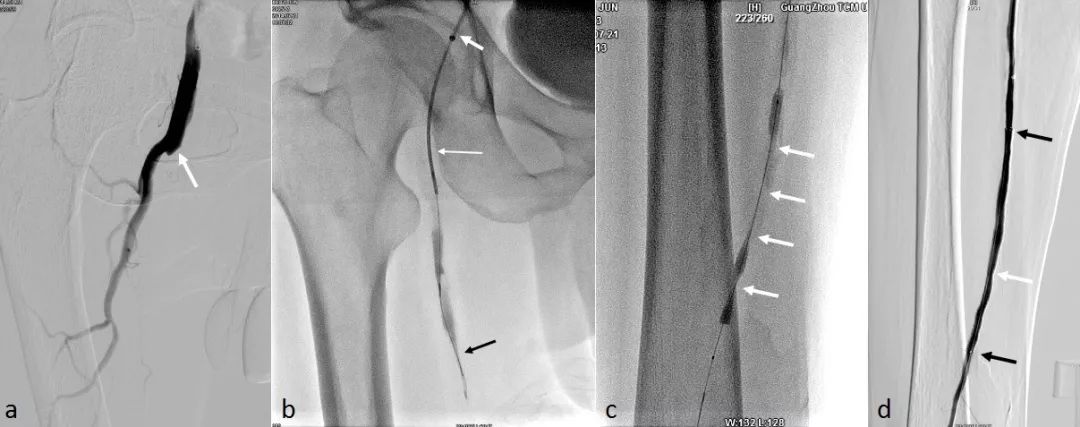

a.白箭处为右股浅动脉起始部闭塞;b.导管鞘(粗白箭)支撑导管(细白箭)并配合导丝(黑箭)开通闭塞;

图中的黑长条就是球囊导管正在对狭窄血管进行扩张成形